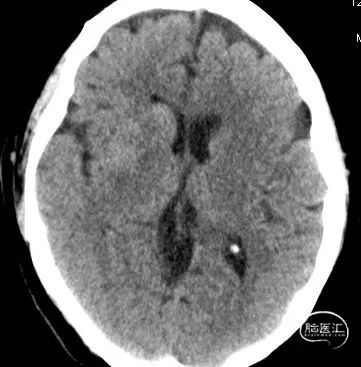

术后即刻复查颅脑CT除外脑出血,予阿司匹林及波立维双联抗血小板治疗。

复查CT见额叶、颞叶局部梗塞灶,无脑出血;康复科会诊协助进行康复训练。

术后即刻复查颅脑CT未见明显脑出血,因患者长期服用华法林钠,取栓后暂未予抗血小板及抗凝治疗。

复查24小时CT见颞叶及基底节区出血,停用并予维生素K拮抗华法林钠,至脑出血吸收后再次启动华法林钠抗凝,维持INR:1.8-2.5(心外科意见)。

术后复查CT见颞叶、基底节区出血灶